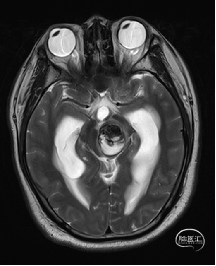

术前MRI检查

术前MRI检查提示左侧丘脑中脑海绵状血管瘤并卒中,梗阻性脑积水;

诊断:1.左侧丘脑中脑海绵状血管瘤并卒中,2.梗阻性脑积水;

根据MRI及DTI显示,只有在丘脑与上丘之间的点(dot)进入病变才可能在切除病变时最大程度保护神经功能,由于上述原因,该“点”在术中显露极其困难,虽有导航指引,电生理监测的条件下,对术者的耐心、技术、经验及体能依然是极大的挑战;

本例患者磁共振检查清晰显示病变位于左侧丘脑中脑区域,且位于丘脑内下方向中脑顶盖延续,病变的上部、前部、外侧部都有重要的神经组织,因此,手术从上方、前方、外侧方向切除病变均难以实施;

从后方有POPPEN入路、Krause入路等,但是因为病变并未充分向松果体区、大脑大静脉后方突出,有大脑大静脉复合体的阻挡,POPPEN入路有较大的难度显露及切除病变,残留的可能性比较大;传统显微镜下进行的幕下小脑上入路在病变的显露及切除上依然有较大的难度。